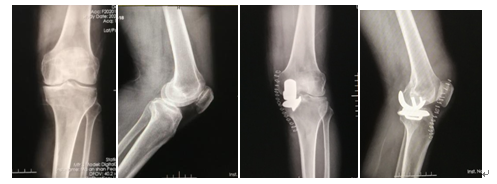

病例2:71歲的男性張某,行“膝關(guān)節(jié)單間室置換術(shù)”治療膝骨關(guān)節(jié)炎,術(shù)后患者非常滿意。